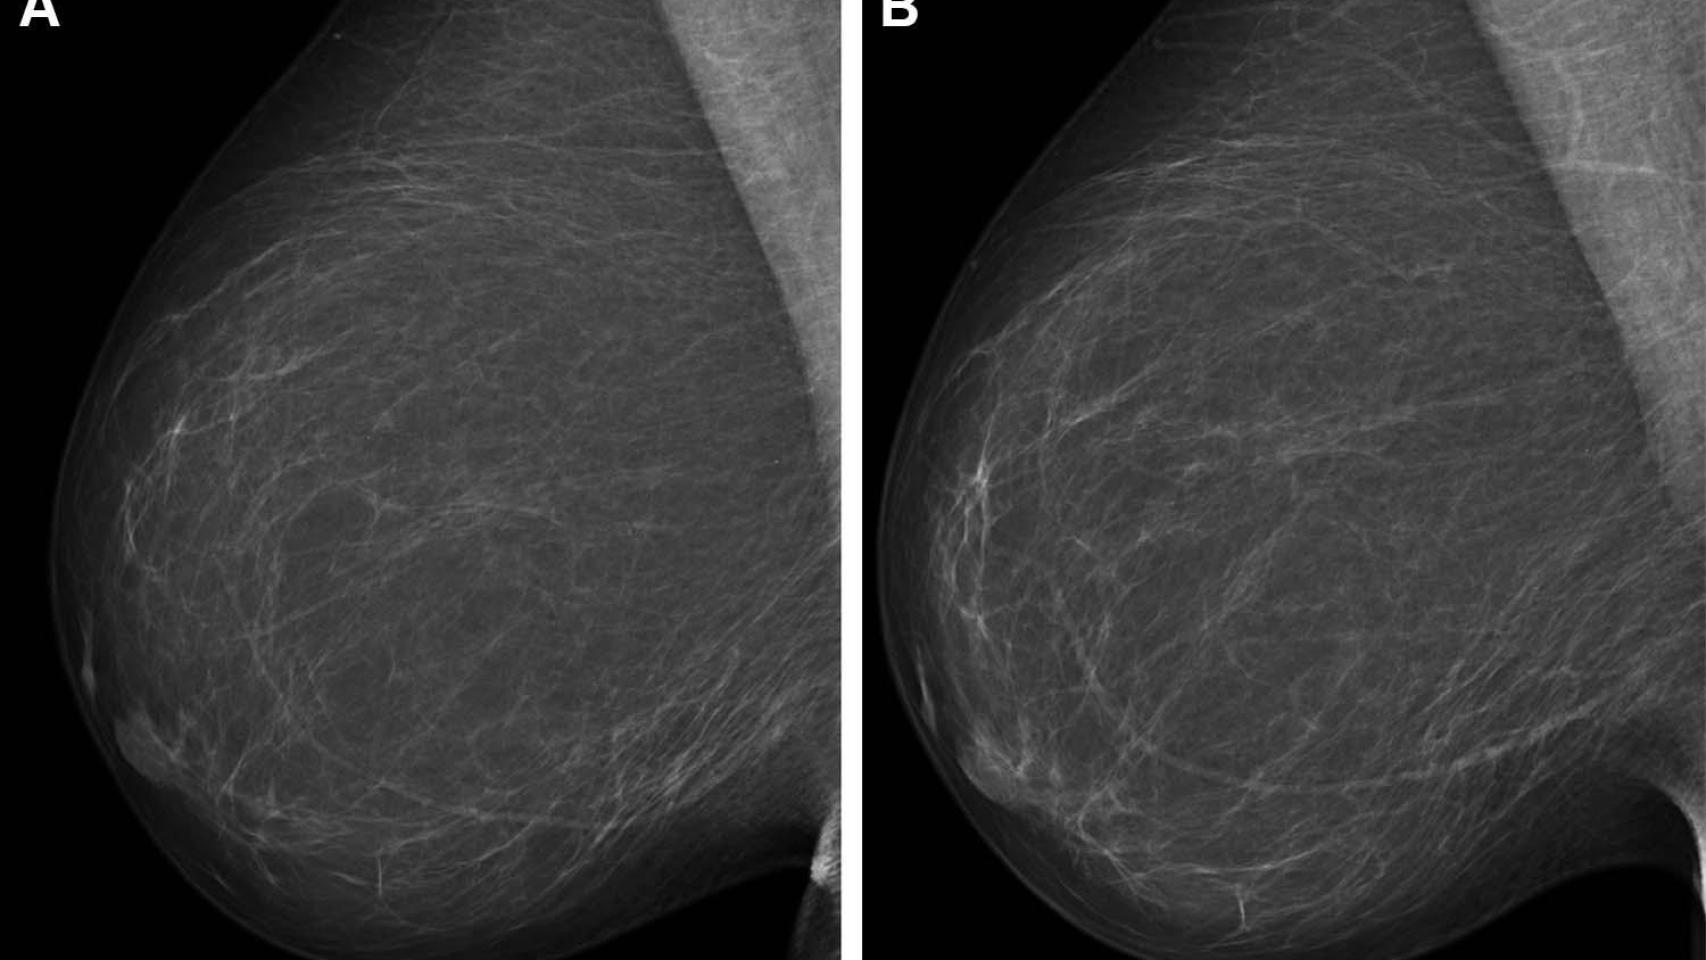

El fallecido, explica Sires, vivía en Madrid. Allí se le detectó un cáncer de pecho. Un "carcinoma de mama izquierdo" que le extirparon y por el que fue tratado en la sanidad madrileña. Le practicaron "mastectomía y vaciamiento axilar", señala su abogado. Eso ocurrió en 2005.

El letrado reconoce que, al tener 86 años, el hombre "no estaba incluido en el programa de cribado de cáncer de mama", pero sí cree que debía haber hecho seguimiento de la enfermedad tratada en Madrid.